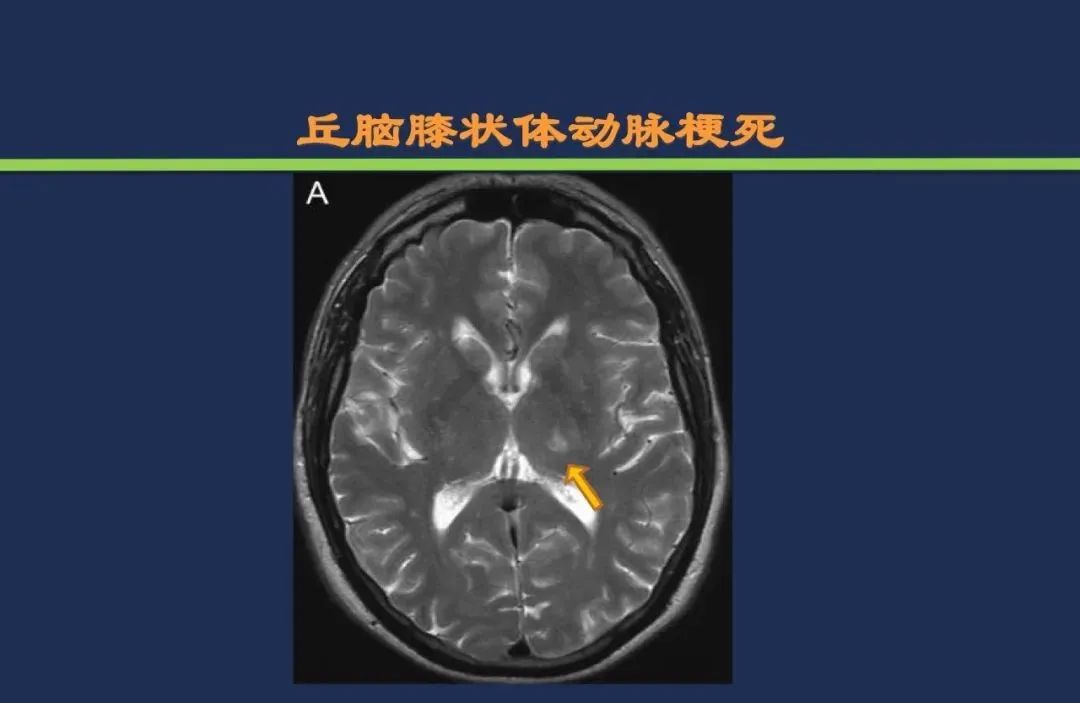

丘脑结节动脉